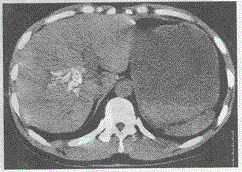

女,55岁,上腹部疼痛三个月,伴有厌食,如图,最可能的诊断是A.肝结核B.胆管结石C.肝内血肿D.胆囊结石E.肝血吸虫病

选项 A.肝结核 B.胆管结石 C.肝内血肿 D.胆囊结石 E.肝血吸虫病

答案 B